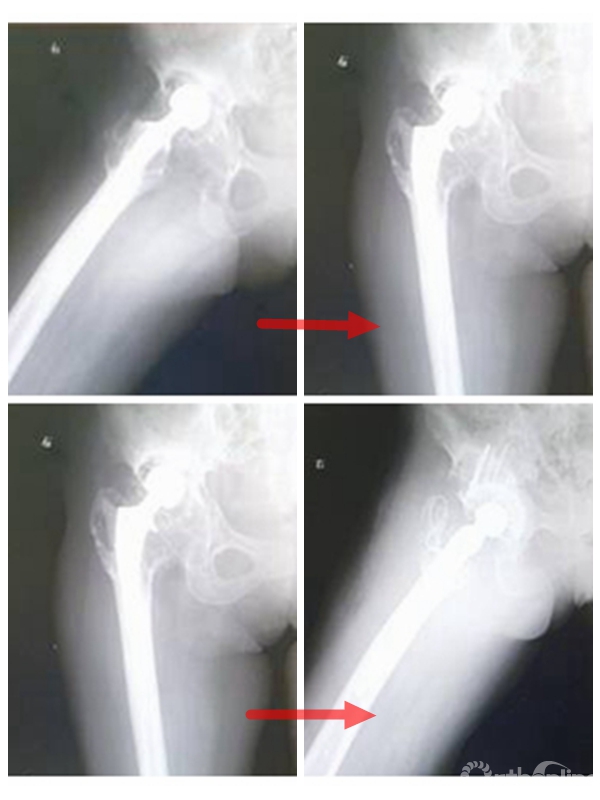

复杂的人工髋关节翻修技术

该科于1974年开展广东省首例人工髋关节置换术,因为早期该科和各医院骨科使用是不成熟的假体,且早期手术缺乏规范和经验,导致患者出现松动的而翻修的病例较多。九十年代以来,该科协助各级医院开展髋关节置换术,接受各级医院转院的翻修病例较多。1999年开始,积极开展了膝关节表面置换术。随着初次置换病例的增多,也出现了需要翻修的病例。针对无菌性松动的病例,该科在人工关节翻修处理与技术方面积累了丰富经验,总结出一定了规律,在国内处于领先地位。

重视患者的术后随访,当复诊时聚乙烯内衬磨损到一定程度,而患者尚未出现明显临床症状前就进行内衬的更换,可以避免大翻修的数量,不仅减少了患者的痛苦,也节约了不少的费用。例如,对严重髋臼骨缺损患者,采用国际最新的CUP-CAGE技术,有效地使得患者的翻修假体生存时间延长。对膝关节置换感染患者,采用二期翻修技术,植入自制含抗生素骨水泥的SPACER,运用膝关节翻修假体,治愈了膝关节置换感染病例。